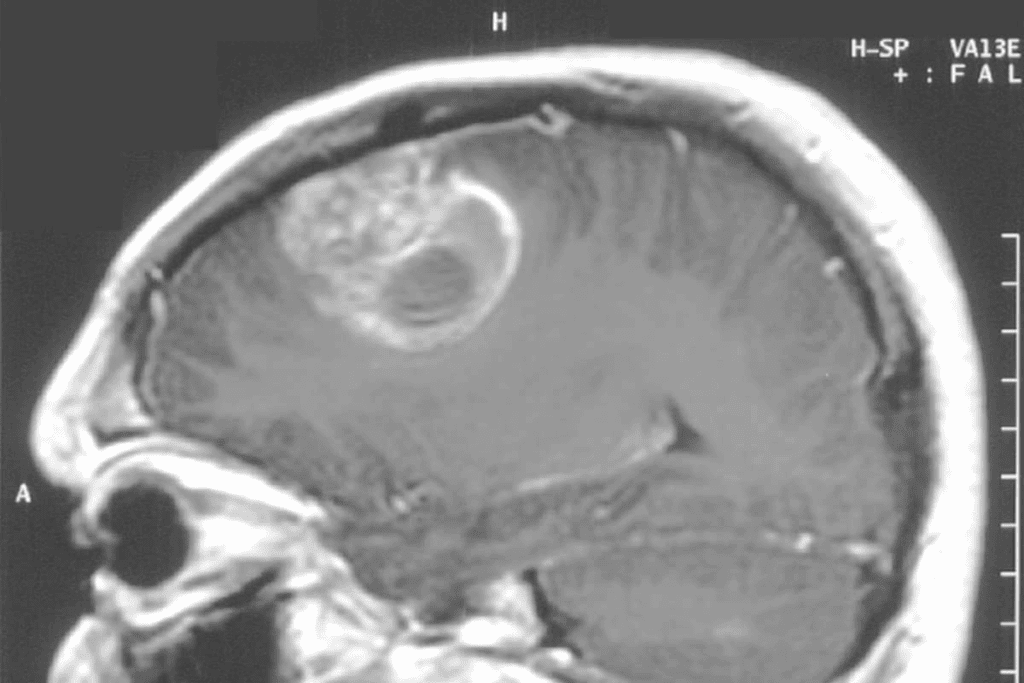

What Brain Tumors Look Like on MRI

Brain tumors look different on MRI scans. It depends on the tumor’s type, size, and where it is. Tumors show up as abnormal masses with special features.

For example, some tumors might look bright on certain images. This helps doctors see how big the tumor is and where it is in relation to other parts of the brain.

Some tumors might look:

- Bright on T2-weighted images because they have a lot of water.

- Darker on T1-weighted images, but they might look brighter after contrast is added.

MRI Brain Tumor vs. Normal Brain Tissue

MRI is great at telling tumors apart from normal brain tissue. Tumors often look different and might get brighter with contrast. But, how they look can change based on the tumor itself.